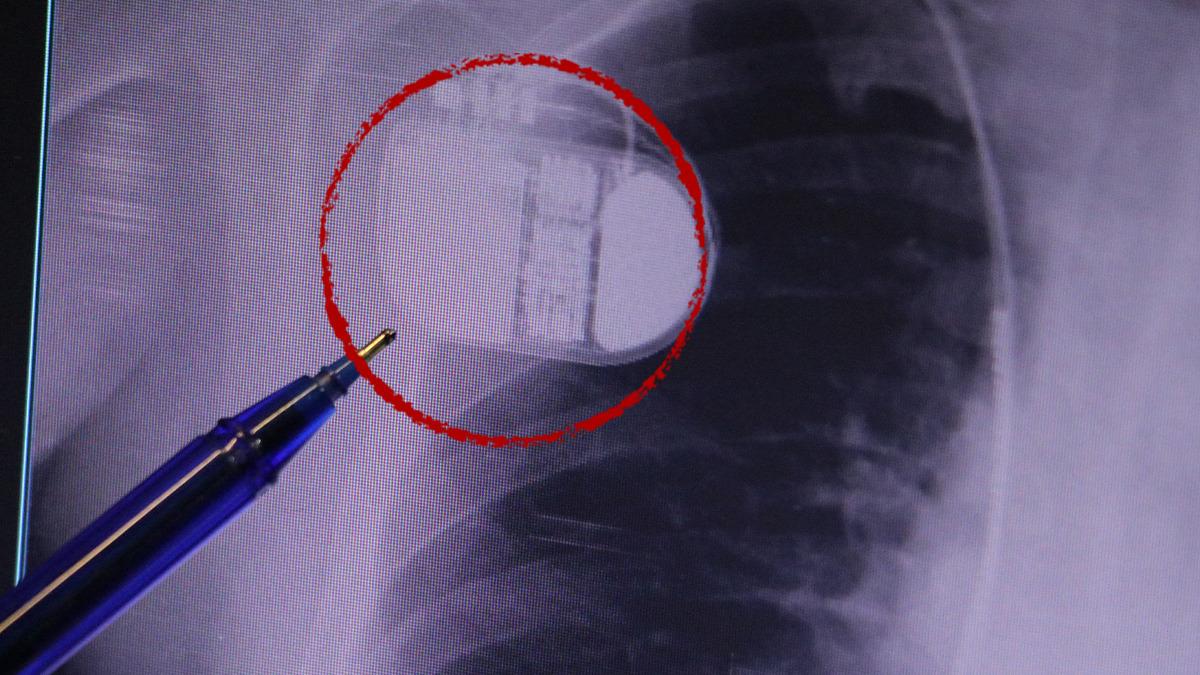

MR makinesine kalp pili takılmasının mümkün olduğunu belirten Erdoğu, şöyle konuştu: “Çok büyük bir ameliyat değil ama yine de ciddi bir cerrahi işlem. Kalp pili tıpta son 30 yılın en büyük gelişmesi. Aslında bilgisayarın minyatürleştirilmiş hali olup insan vücuduna yerleştirilen bir tedavi. İnsan ömrünü önemli ölçüde uzatan bir tedavi. İnsanlar şokla hayata tutunurken, pil olmasaydı öleceğini düşündüğümüz çok sayıda hastamız var. Bu özelliğimiz Kalp pili uygun hastalarda ani ölümü önler, ritmi düzeltecek sağlık çalışanı veya defibrilatör yoksa hastayı hayatta tutmak mümkün değildir. Hastalarımız “kalp pilim var” dediğinde hastalıktan kurtulurlar. Örneğin, mikser kullanmak veya kolu sallayacak herhangi bir hareket kalp pilini olumsuz etkileyebilir. Soğuk havalarda vücutta meydana gelen şiddetli titremeler kalp pilinin hafızasını karıştırıp gereksiz şoklara neden olabilir.